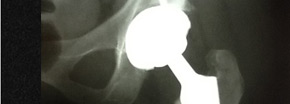

Reemplazo de cadera

Prótesis de cadera